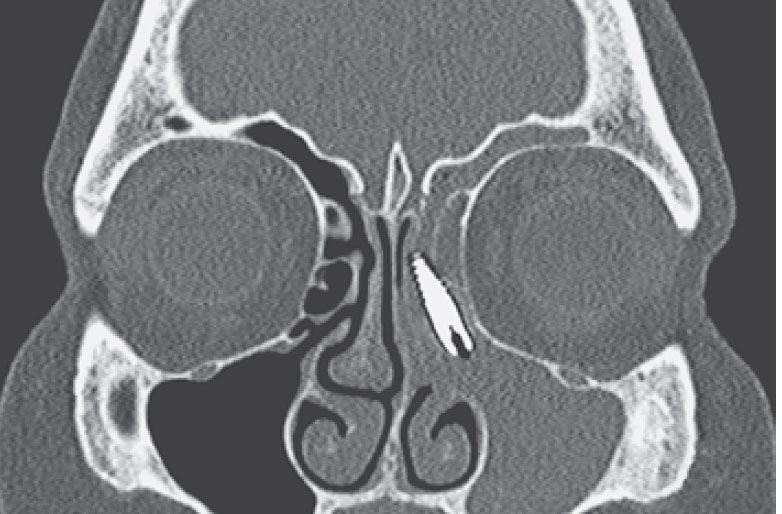

Imagine entrar no dentista para colocar um implante e descobrir [...]

As doenças conhecidas por atrofia de maxila e atrofia de [...]